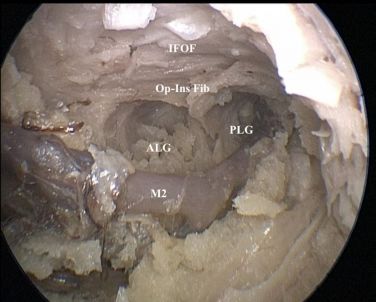

沿皮质切口垂直深入直达岛叶(图3),下额枕束(IFOF)于岛下沟下方进入侧脑室颞峡,是常用的解剖标志。

图3. 岛下沟的显微镜下观察。

图5. 内镜下观察。下额枕束(IFOF)在岛叶下方走行,M2分支走行于岛叶表面,岛长回后部软膜切除时血管无损伤。